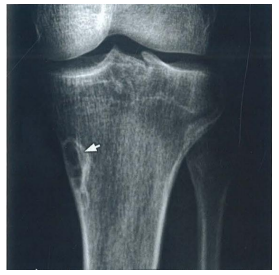

Radiografia realizada em paciente do sexo masculino de 17 anos demonstra a lesão radioluminescente com bordas escleróticas apontada pelas setas na figura. O diagnóstico

CORRETO

é:

A

Fratura por estresse.

B

Displasia fibrosa.

C

Osteoma osteóide.

D

Defeito fibroso cortical.